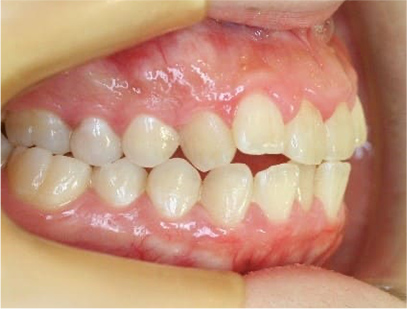

症例03

前歯が咬み合ってなく開咬の症例

上下の前歯が咬んでない事と前歯のデコボコを主訴として来院されました。

通常通り検査を行い「前歯部にデコボコを伴う開咬」と診断されました。

治療計画

舌の悪習癖のために上顎の歯並びの幅が狭いために裏側から拡大し、その後、上顎には裏側に下顎には表側に矯正装置を装着して綺麗に歯を並べてまた咬み合わせも改善しました。

矯正の種類

上は裏側に、下は表側にセラミック(白い矯正装置)

治療前

• 正面

• 上側

• 下側

• 右側

• 左側